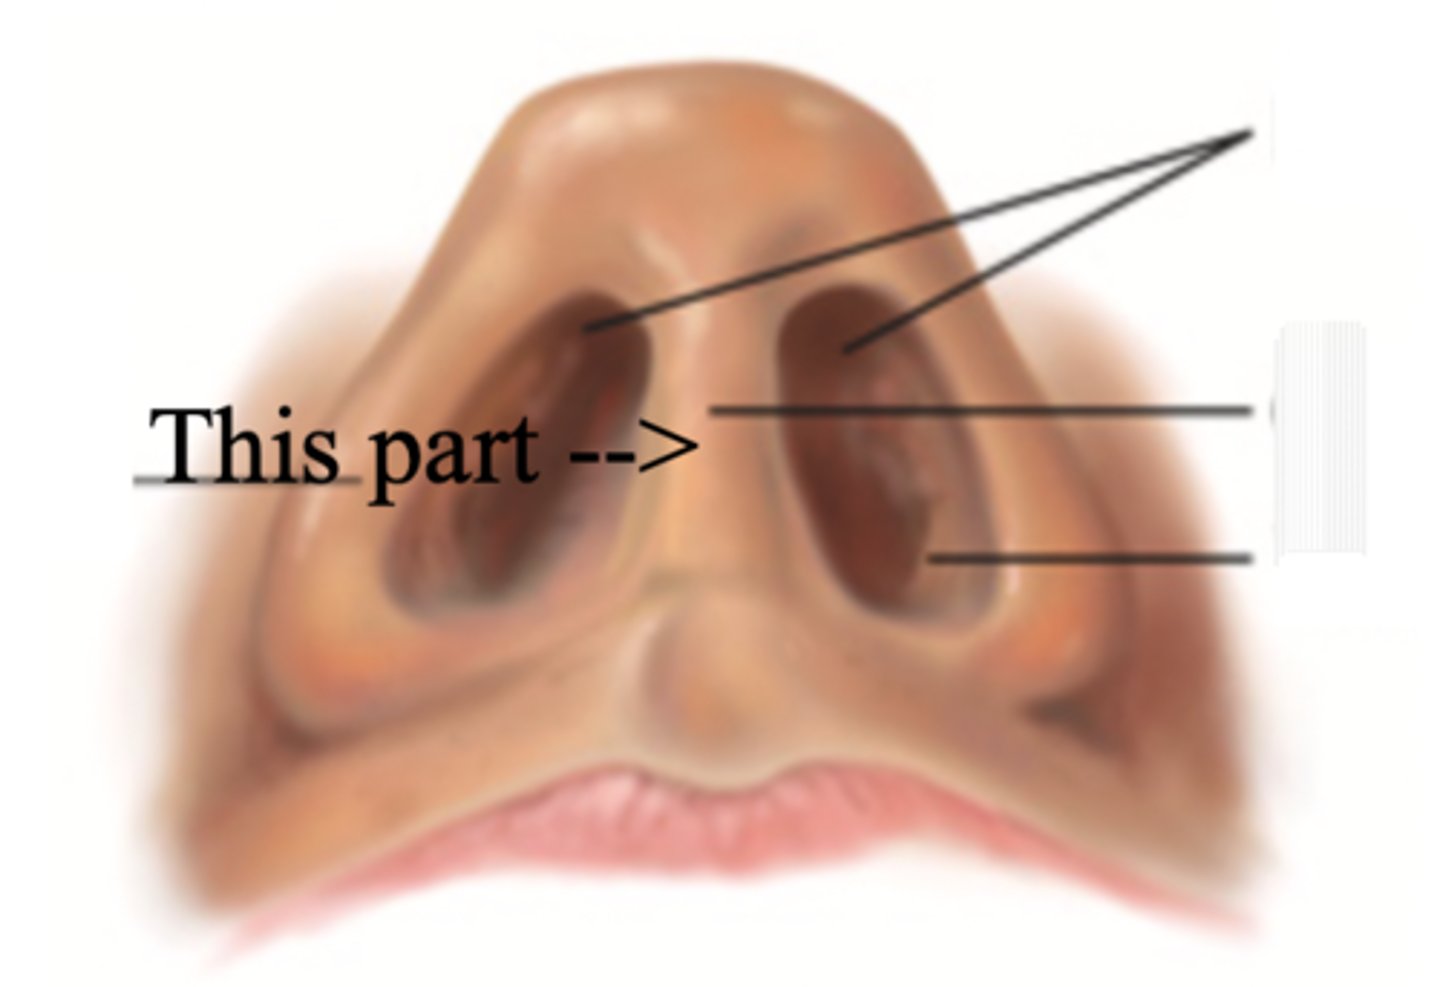

Nose

Organ of smell

Bridge

Tip

Ala

Nares

Columella

Vestibule